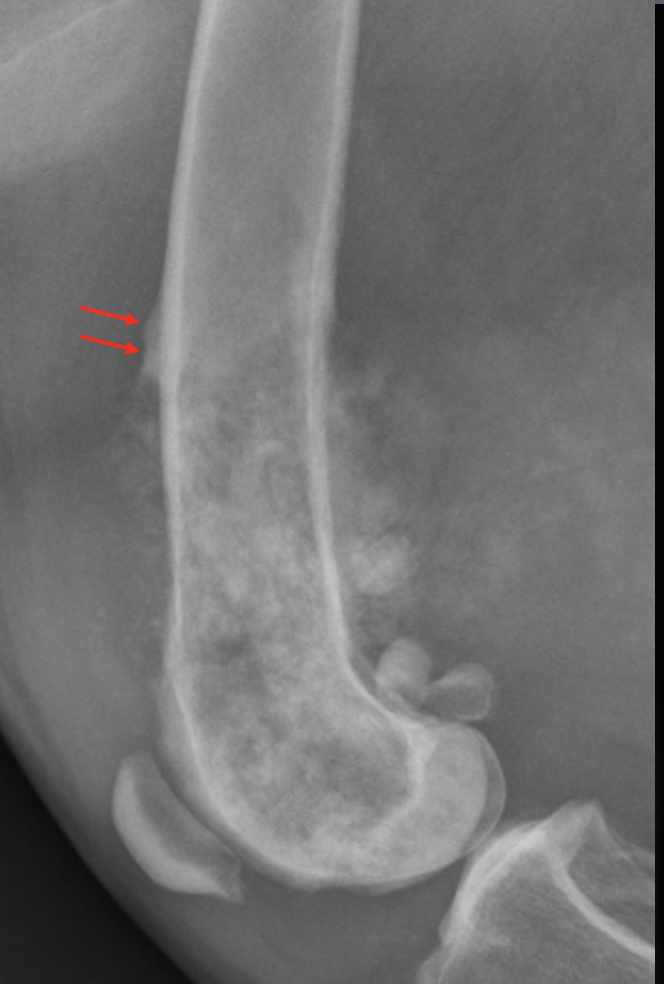

What is shown in this radiograph at the arrows?

Codman’s triangle